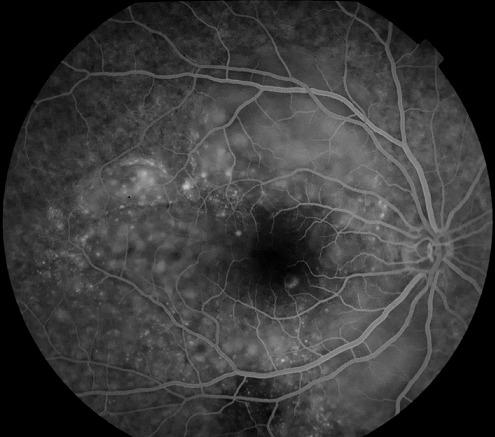

[Vogt-Koyanagi Harada syndrome in its purely ocular form: about a case].

[Vogt-Koyanagi Harada syndrome in its purely ocular form: about a case].[纯眼部形式的Vogt-小柳原田综合征:病例报告]